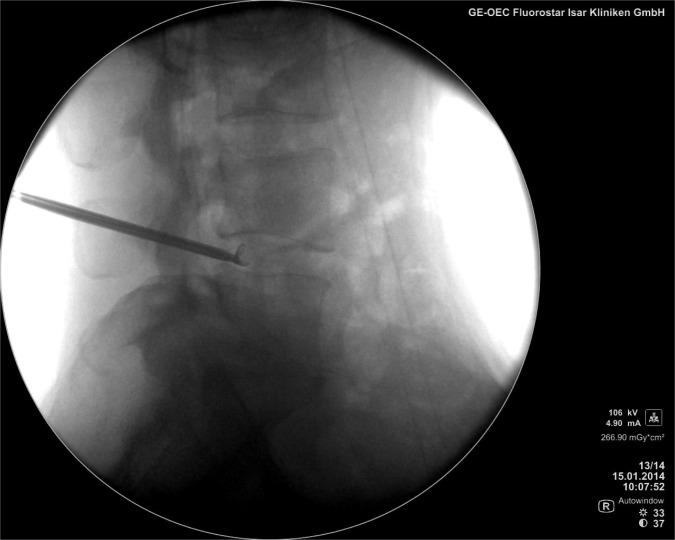

Patients with radiculopathy caused by contained disc herniations are less likely to have good outcomes following discectomy surgery than patients with disc herniations that are not contained. The author presents his 4-year results from a prospective trial regarding the efficacy and safety of a tubular transforaminal radiofrequency-assisted manual decompression and annulus modulation of contained disc herniations in 58 patients.

METHODS

Fifty-eight patients with lumbar radiculopathy due to a contained disc herniation were enrolled in a prospective clinical study. Visual analog scores (VAS) for back pain and leg pain, quality of life assessment, Macnab criteria, and SF-12 were collected from patients before treatment, at 2-years and 4-years post-treatment.